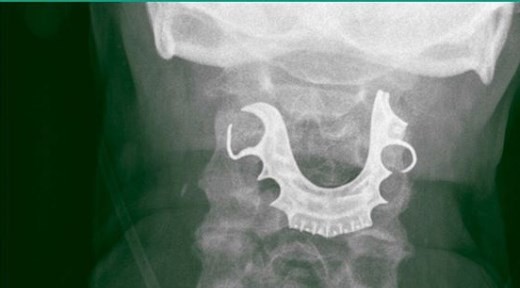

Sufrió quemaduras por una descarga eléctrica que pasó del cargador de su celular al collar que llevaba puesto